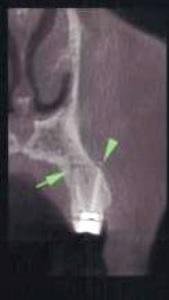

Полость корневых каналов промыли физиологическим раствором и восстановили зуб с помощью материалов для временного пломбирования. Чтобы предотвратить риск инфекции, в течение трех дней внутримышечно пациентке вводили клиндамицин (600 мг дважды в день), и также назначили ибупрофен (400 мг) для купирования боли, который она принимали по мере необходимости. Экстренное наружное использование холодных компрессов в первый день сменили на теплые компрессы во второй день для лечения отека. На первом повторном визите отмечалось увеличение кровоподтека, хотя припухлость значительно уменьшилась (фото 3). Отек и кровоподтек постепенно исчезали в течение всего периода наблюдения, а на 10 день после процедуры у пациентки исчезли все беспокоившие ее симптомы (фото 4). Для оценки соотношения между зубом, альвеолярным отростком и верхнечелюстной пазухой была проведена дентальная объемная томография (dental volumetric tomography — DVT) (NewTom 3G, QR SRL, Верона, Италия). На DVT-изображении было обнаружено, что апекс щечного корня перфорирует кортикальную пластинку верхнечелюстной кости, создавая, таким образом, свободный путь для проникновения ирригационного раствора в мягкие ткани (фото 5 (а) и фото 5 (б)). Через 10 дней симптомы полностью исчезли. В то же время в корневой канал наложили повязку с гидроксидом кальция. Во время заключительного посещения примерно через 4 недели после предыдущей процедуры корневые каналы запломбировали материалом AH Plus (Dentsply Maillefer) и гуттаперчей (фото 6).

Фото 5: (а) Изображение 3D и (б) коронарный вид DVT показали, что верхушка щечного канала перфорирует кортикальную пластинку верхней челюсти.